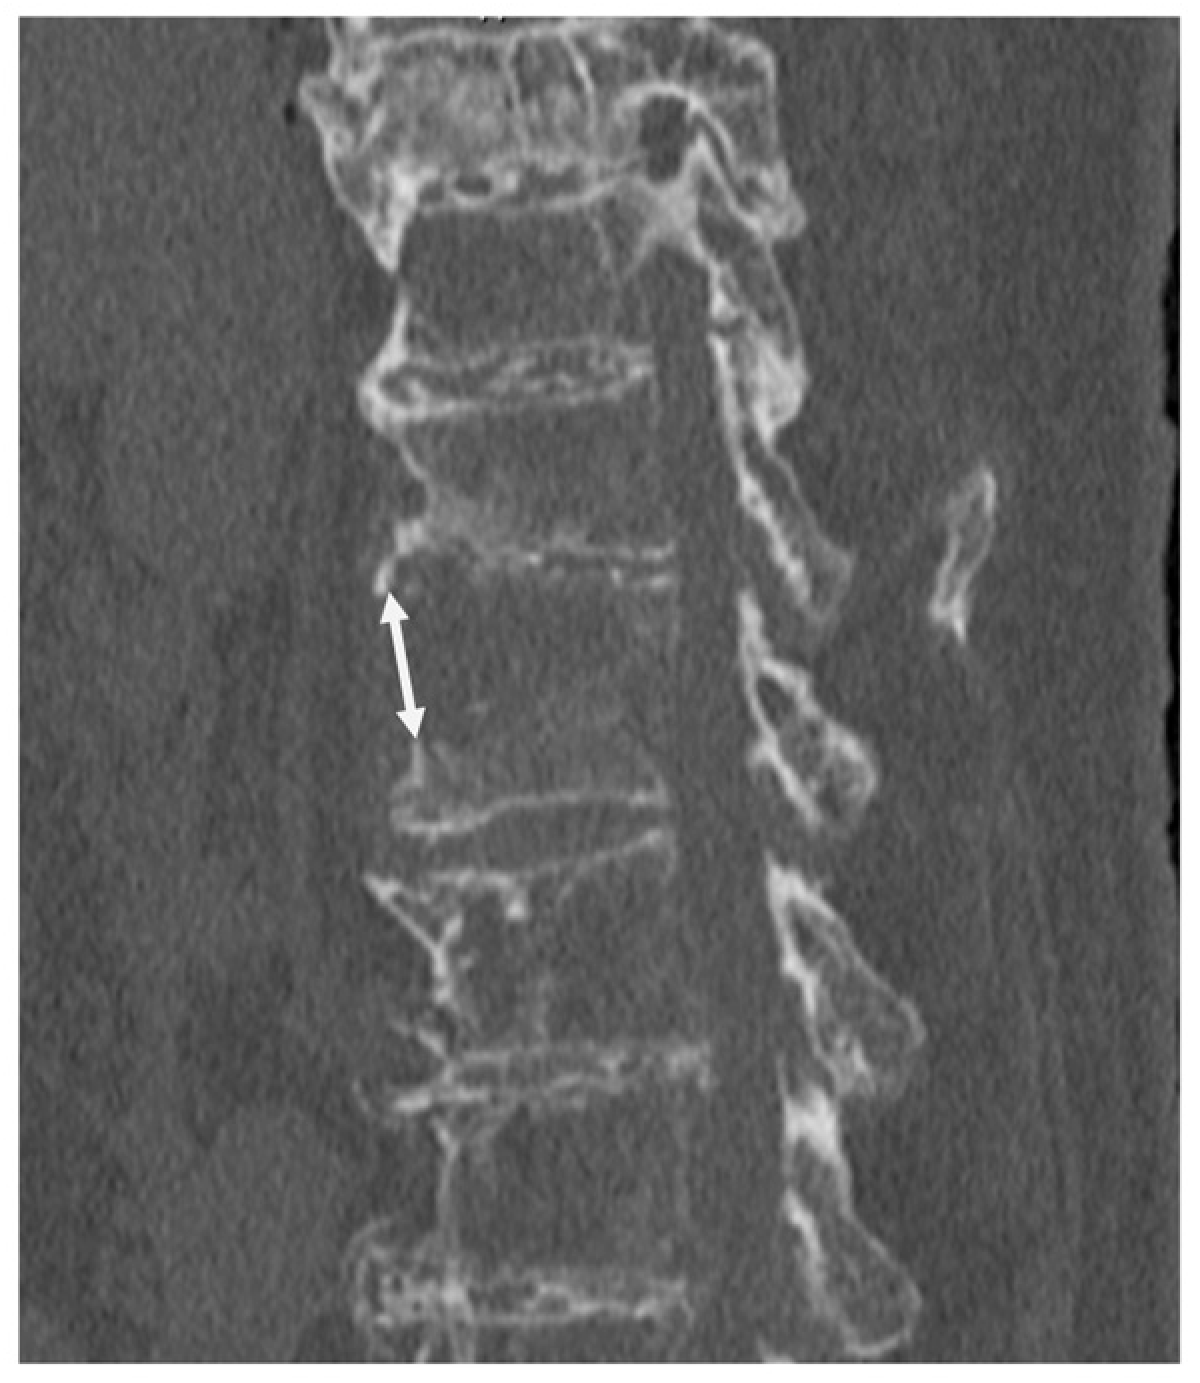

3.1. Case Presentation 1